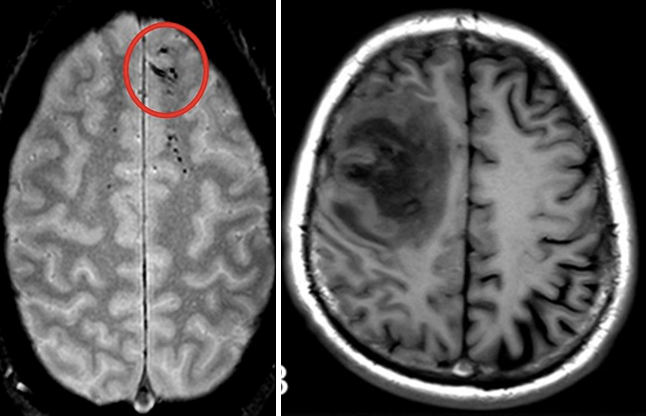

Image

Two horizontal cross sections are shown, each of which features a region of damaged brain, appearing as an unusual dark section.

Examples of lesions include a brain microbleed (left) and a lesion in the left frontal lobe (right). Image credits: National Institute of Neurological Disorders and Stroke/NIH (left); adapted from "CT and MRI scan of the brain with melioidosis" by Wei-yuan Huang, Gang Wu, Feng Chen, Meng-meng Li and Jian-jun Li is licensed under CC BY 4.0 (right)